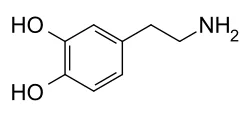

In this article we will look at a specific chemical called dopamine and explore how it affects our brains when we use pornography.

Dopamine is a chemical located in the brain that is closely tied with emotions and actions. Its primary function is to carry signals between nerve cells (neurons) in the brain as a neurotransmitter.

What dopamine is best known for—and what we are most interested in—is its association with the reward center of our brain. It is considered to be the major player in reward-motivated behavior.

Dopamine is responsible for those feelings of excitement about getting something new, or doing something that you love. It is the chemical that signifies happiness and enjoyment.

Dopamine is typically considered to be responsible for learned behaviors, but new research suggests that dopamine is involved with ongoing actions as well. We usually consider dopamine when talking about reward-based behavior (classical learning), when our actions depend upon the type of reward they promote. When a reward produces dopamine we feel good, and thus, we are more likely to repeat the action to continue feeling good.